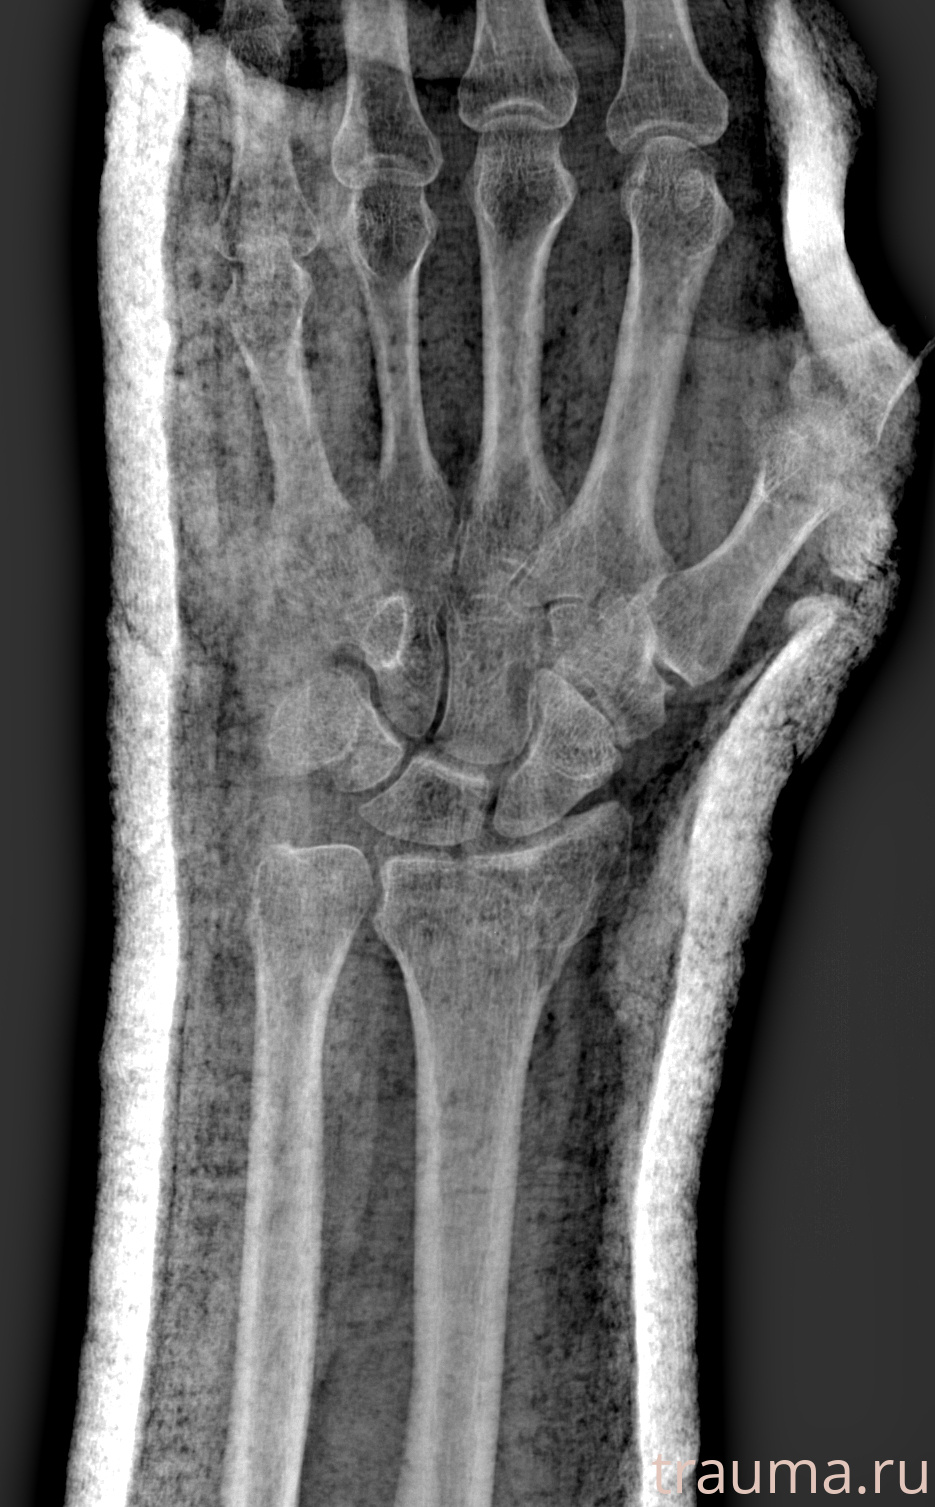

Рентгенограммы

Рентген на дому: по вашему адресу приезжает врач-рентгенолог, травматолог-ортопед с мобильным рентгеновским аппаратом, проводит диагностику травмы или заболевания, делает необходимые рентгенограммы, дает рекомендации по дальнейшему лечению. Получить качественные снимки в домашних условиях возможно благодаря уникальной методике, разработанной МосРентген Центром для института  Склифосовского